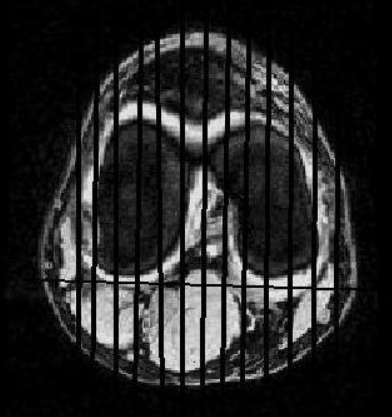

- Use Ax slices to prescribe sagittal slices (see image for Sag prescription)

- Prescribe the Sagittal slices perpendicular to the Coronal slices as shown on image below.